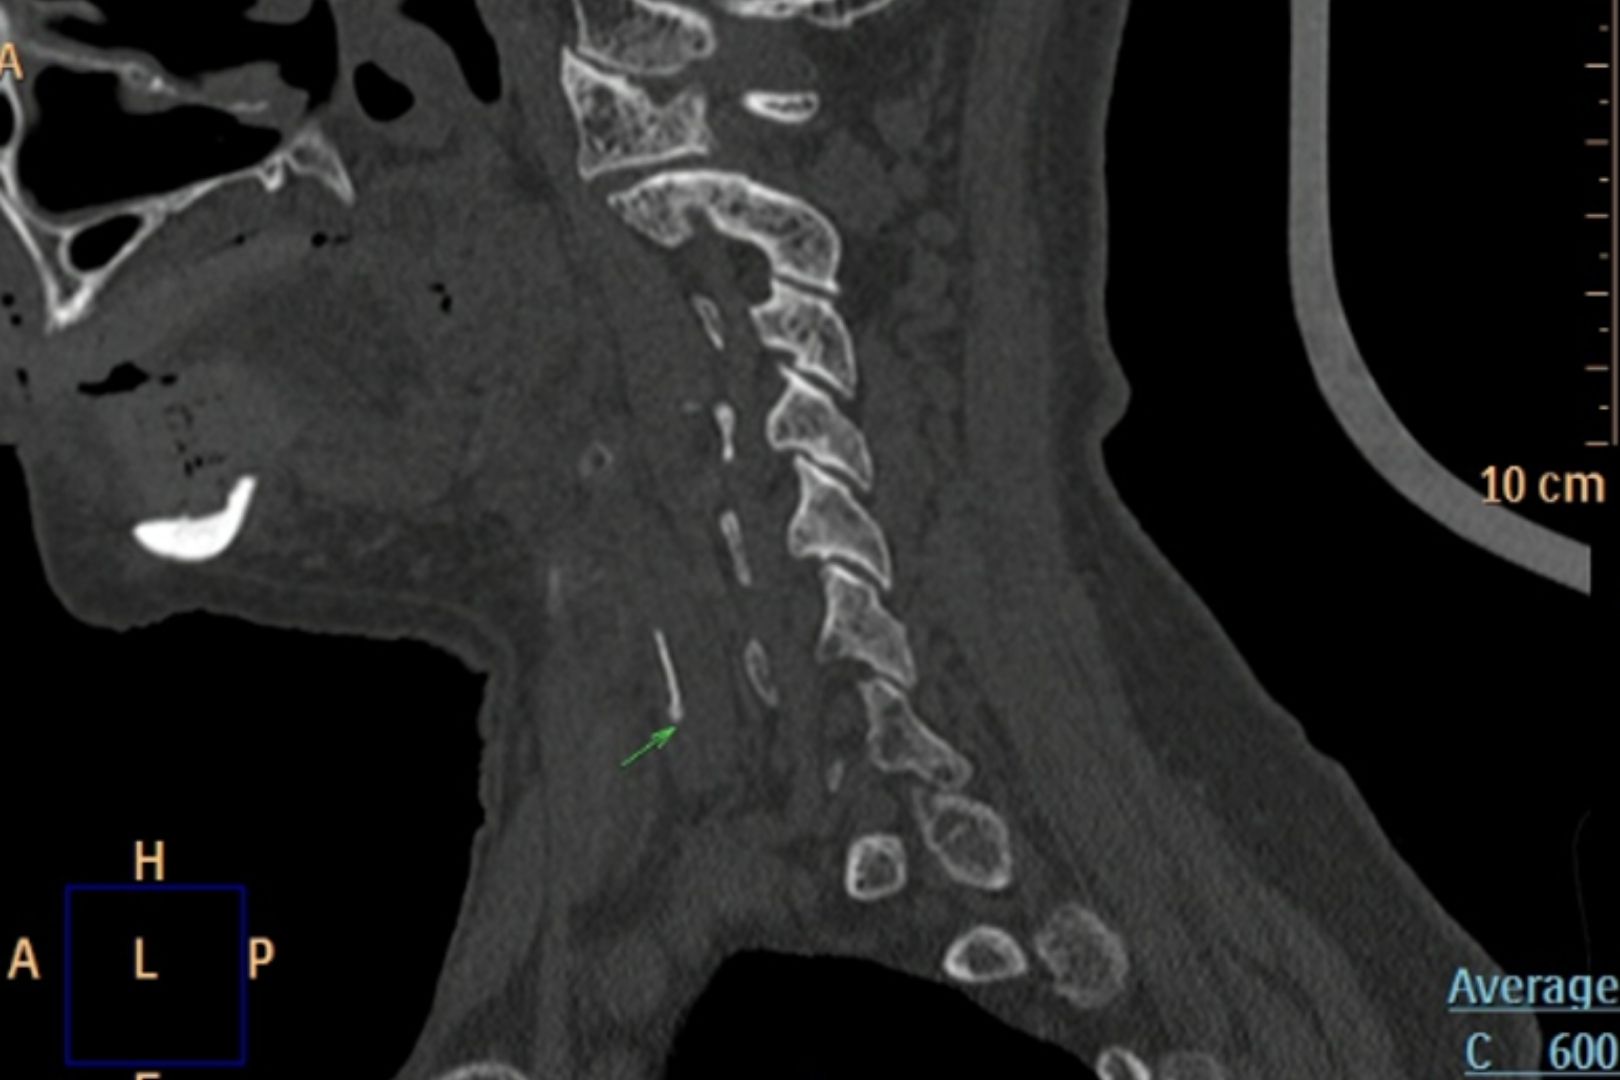

Trước tình trạng lâm sàng nuốt đau rất rõ rệt của bệnh nhân, các bác sĩ đã quyết định thực hiện các cận lâm sàng chuyên sâu hơn. Sau khi kết quả X-quang cổ nghiêng nghi ngờ có dị vật, bệnh nhân được chỉ định chụp CT-scan.

Kết quả hình ảnh đã khiến ekip điều trị bất ngờ: Một mảnh xương cá kích thước khoảng 1x22mm đã đâm xuyên hoàn toàn qua niêm mạc đường tiêu hóa, nằm ra ngoài ống thực quản và xuyên sâu vào thùy trái của tuyến giáp.